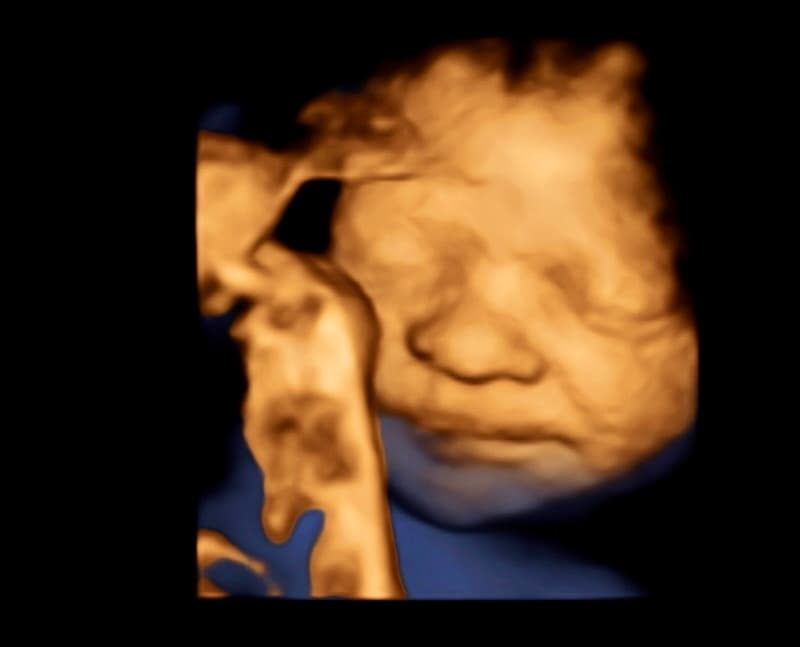

At Magnolia Fetal Imaging, we provide a warm, relaxing environment where you can bond with your baby through advanced 3D/4D & HD ultrasound technology. Our studio focuses on capturing precious keepsake moments for families — gender reveals, early looks, and high‑definition images you will cherish for a lifetime.

All sessions are non‑diagnostic and designed purely for bonding and keepsake entertainment.